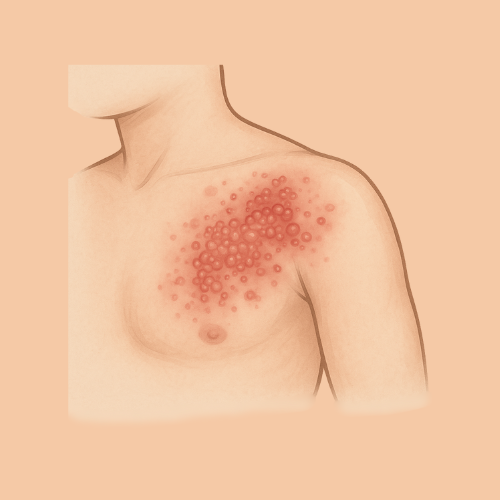

Find Relief by Symptom or Skin Concern

EMUAID is designed to relieve symptoms from over 100 difficult-to-treat conditions like eczema, psoriasis, nail fungus, hemorrhoids, shingles, acne, rashes, burns, cellulitis, and more. If it's red, itchy, cracked, painful, or inflamed- EMUAID may help.